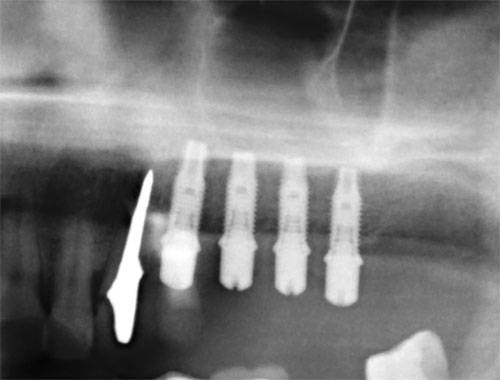

Синус-лифтинг (поднятие дна гаймеровой пазухи). Данная процедура относится только к верхней челюсти. Проводится в случаях недостаточной высоты кости между краем костного гребня верхней челюсти и дном гаймеровой (верхнечелюстной) пазухи.

Различают открытый и закрытый синуслифтинг по способу доступа к пазухе. Закрытый — это доступ через отверстие импланта, а открытый — это боковой доступ через преддверие полости рта.

Принцип операции в том, что через любой из доступов, в пазуху вводится костное вещество, которое превращается в собственную кость в течение полугода. В зависимости от толщины альвеолярного отростка зубные имплантаты могут быть установлены либо одновременно с выполнением синус-лифтинга, либо через некоторое время после заживления участка.